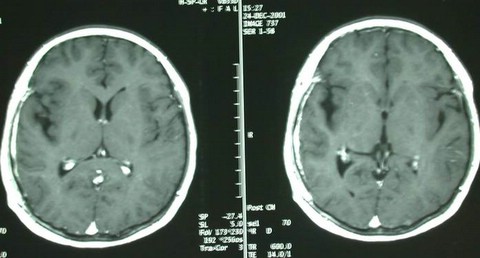

右颞深部胶质瘤

男性,40岁,主因,癫痫发作入院,查MRI示:右颞胶质瘤。

术后复查